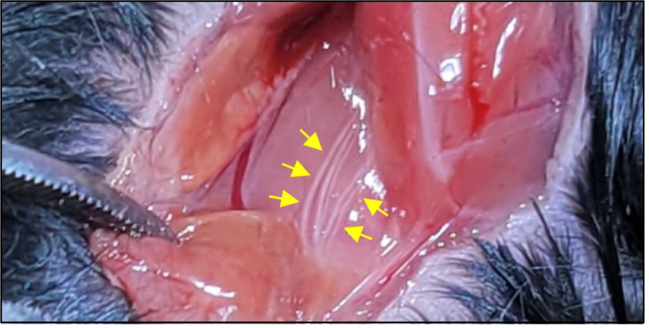

신경면역학 실험실(이찬희 교수님)

biomedical_JW_MS_K2WT001_S